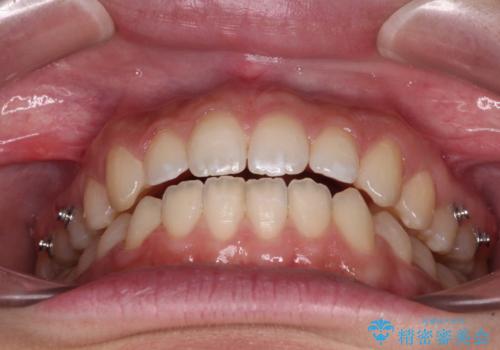

【モニター】隙間だらけの前歯を治したい インビザラインによる矯正治療

- 上下前歯の隙間と咬み合わない前歯を気にして来院された患者様です。

開咬の治療は、前歯を閉じるように動かすとともに、上下臼歯を圧下(骨内にめり込ませる)させることで進めて行きます。

インビザラインは臼歯の圧下を効果的に行えるため、インビザラインを用いて矯正治療を行うこととしました。

仕上がりとしては、もう少し上下前歯を接触させたかったのですが、ここまで改善されたことで患者様は大変満足され、治療を終えることとなりました。